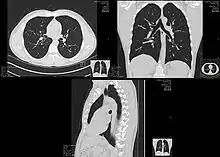

Lungs

A CT scan can be used for detecting both acute and chronic changes in the lung parenchyma, the tissue of the lungs.[41] It is particularly relevant here because normal two-dimensional X-rays do not show such defects. A variety of techniques are used, depending on the suspected abnormality. For evaluation of chronic interstitial processes such as emphysema, and fibrosis,[42] thin sections with high spatial frequency reconstructions are used; often scans are performed both on inspiration and expiration. This special technique is called high resolution CT that produces a sampling of the lung, and not continuous images.[43]

Bronchial wall thickening can be seen on lung CTs and generally (but not always) implies inflammation of the bronchi.[44]

An incidentally found nodule in the absence of symptoms (sometimes referred to as an incidentaloma) may raise concerns that it might represent a tumor, either benign or malignant.[45] Perhaps persuaded by fear, patients and doctors sometimes agree to an intensive schedule of CT scans, sometimes up to every three months and beyond the recommended guidelines, in an attempt to do surveillance on the nodules.[46] However, established guidelines advise that patients without a prior history of cancer and whose solid nodules have not grown over a two-year period are unlikely to have any malignant cancer.[46] For this reason, and because no research provides supporting evidence that intensive surveillance gives better outcomes, and because of risks associated with having CT scans, patients should not receive CT screening in excess of those recommended by established guidelines.[46]

Computed tomography angiography (CTA) is a type of contrast CT to visualize the arteries and veins throughout the body.[47] This ranges from arteries serving the brain to those bringing blood to the lungs, kidneys, arms and legs. An example of this type of exam is CT pulmonary angiogram (CTPA) used to diagnose pulmonary embolism (PE). It employs computed tomography and an iodine-based contrast agent to obtain an image of the pulmonary arteries.[48][49][50]